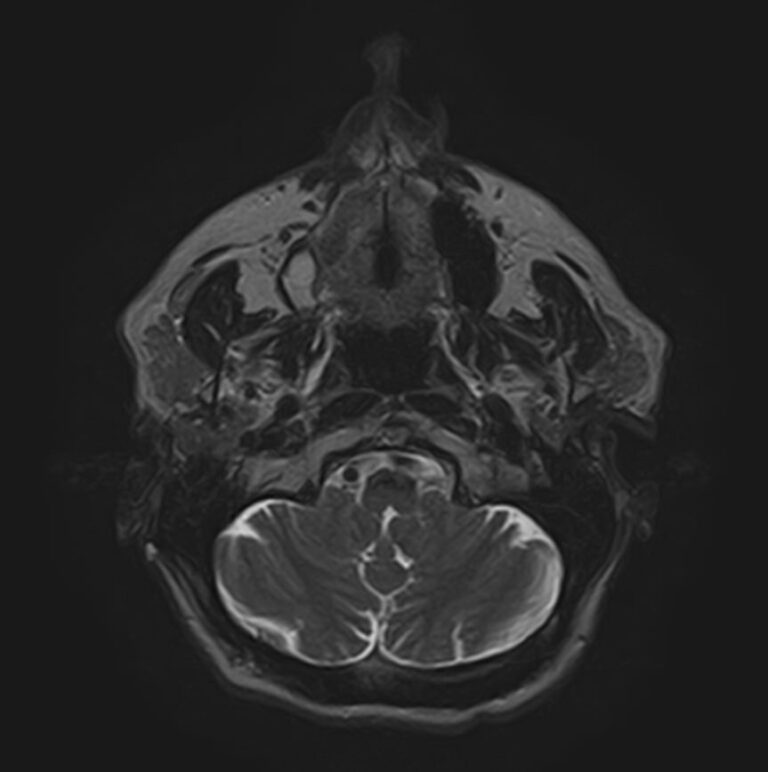

Магнитно-резонансная томография (МРТ) мягких тканей лица – это неинвазивное диагностическое исследование, которое использует магнитное поле и радиоволны для получения детализированных изображений структур мягких тканей в области лица. МРТ мягких тканей лица позволяет визуализировать мышцы, жир, нервы, сосуды и другие мягкотканные структуры, что помогает в диагностике различных заболеваний и патологий, таких как:

Перед проведением МРТ мягких тканей лица обычно требуется консультация врача, который определит необходимость и целесообразность исследования, а также даст рекомендации по подготовке. В некоторых случаях может понадобиться введение контрастного вещества для улучшения визуализации структур и выявления патологий.